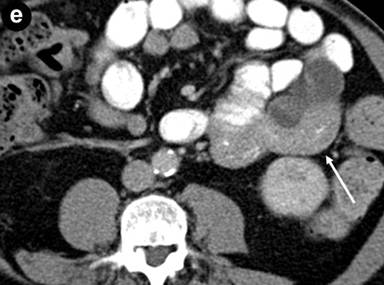

The patient was referred to our institution for consultation where he underwent repeat multiplanar MDCT with the use of 100 mL intravenous (iopromide; Ultravist® 300, Bayer, NJ, USA) contrast material delivered at 3 mL/s and imaged with a 70 s delay. Nine hundred mL oral (water) contrast was also utilized. Images were obtained at 120 kVp and 200 mAs and reconstructed at 5 mm. The pancreas was universally enlarged with a distinct rim of hypoattenuation (Figure 1). The wall of the gastric body and fundus, predominantly posteriorly, was diffusely thickened, measuring up to 1.4 cm, and had a nodular appearance (Figure 1). The gastric wall thickening spared the antrum. No hyperenhancement of the gastric wall was noted. There were additionally noted several hypodense lesions in both kidneys that were surrounded by hypovascular soft tissue (Figure 1) as well as focal jejunal wall thickening without hyperenhancement (Figure 1).

Figure 1. a. Axial MDCT image of the abdomen with intravenous and oral contrast demonstrates a thickened, “sausage-like” pancreas with a hypodense rim of tissue (arrow). b. Axial MDCT image of the abdomen with intravenous and oral contrast demonstrates a thickened and nodular appearance of the stomach wall at the level of the gastric body measuring up to 1.4 cm (arrow). c. Sagittally reformatted MDCT image of the abdomen shows the thickened and nodular gastric body wall, most pronounced posteriorly (arrow). d. Axial MDCT image demonstrates bilateral renal lesions (arrows) with a soft tissue attenuation within and immediately adjacent to the left kidney (dotted arrow). e. Axial MDCT image demonstrates focal jejunal wall thickening. |